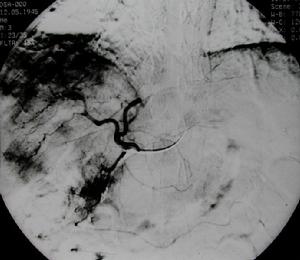

【肝癌的血管造影檢查】

血管造影檢查可快速準確檢測出2公分以下的小肝癌,但因其創傷性較大臨床較少用。